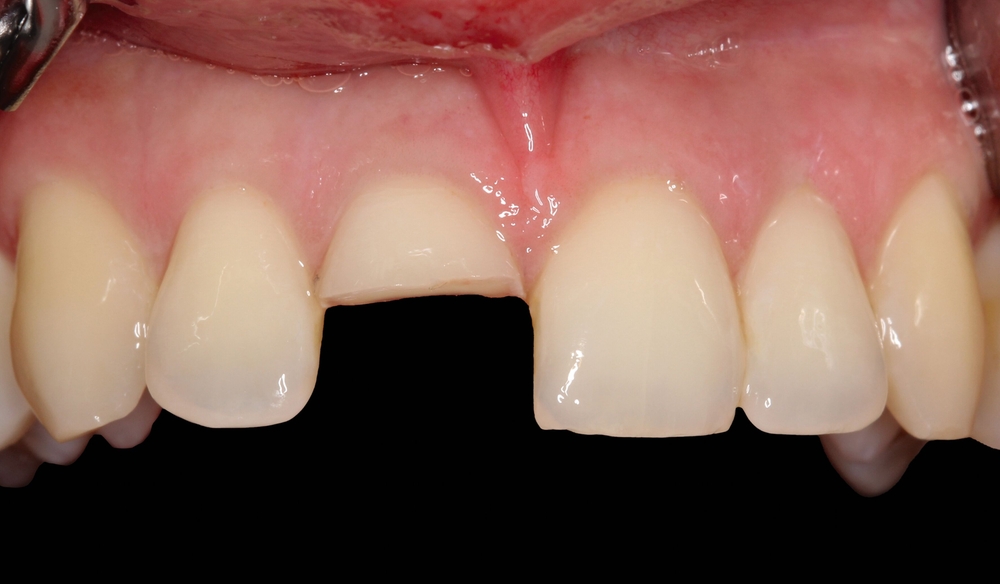

Nach Abtastung der Schädelbasis sowie der Trigeminusdruckpunkte ergab sich kein Anhalt für eine Schädelverletzung. Extraoral zeigten sich eine Schwellung und eine Rötung der Ober- und der Unterlippe. Intraoral zeigte sich eine Kronenfraktur an Zahn 11 (Abbildung 1a), die Pulpa war exponiert und es lag eine Sulkusblutung palatinal vor (Abbildung 1b). Auf Kälte reagierten die Zähne 13—23 sensibel. Die Perkussion an Zahn 11 war stark positiv, die Sondierungstiefen palatinal waren physiologisch.

Eine Alveolarfortsatzfraktur konnte nach Abtastung ausgeschlossen werden. Auf dem Ausgangsröntgenbild zeigten sich an 11 eine koronale Transluzenz, die bis zur Pulpakammer extendiert war, sowie ein leicht transluzenter Spalt auf Höhe des mittleren Wurzeldrittels (Abbildung 2). Eine Wurzelquerfraktur an 11 konnte daher angenommen werden. Die Dislokation der beiden Fragmente betrug röntgenologisch weniger als ein Millimeter.

Die Behandlung erfolgte unter absoluter Trockenlegung mit Kofferdam. Im ersten Schritt wurde eine partielle Pulpotomie an Zahn 11 mit Entfernung von circa 2-3 mm Pulpagewebe mit einem sterilen Diamanten durchgeführt. Die Pulpa stellte sich durchweg hellrot und ausreichend perfundiert dar.

Nach vierwöchiger Schienungszeit reagierte Zahn 11 weiterhin reproduzierbar auf Kälte mit einer leicht erhöhten Mobilität des koronalen Fragments (Lockerungsgrad I). Einen Monat später wurde der Zahn mit einer definitiven ästhetischen Kompositfüllung versorgt.

Bei allen Folgeuntersuchungen nach einem, drei und neun Monaten zeigte sich eine reproduzierbare und plausible Reaktion des Zahnes 11 auf den Kältereiz. Radiologisch waren keine apikalen oder parodontalen Pathologien erkennbar. Bereits circa drei Monate nach der Erstversorgung mit Biodentine zeigte sich eine radiologische Opazität unterhalb der Pulpaüberkappung, die als Dentinbrücke interpretiert werden kann (Abbildung 5).

Bei der klinischen Kontrolluntersuchung nach einem Jahr zeigten sich gesunde parodontale Verhältnisse ohne erhöhte Beweglichkeit des Zahnes 11; die Kältereaktion war weiterhin reproduzierbar und plausibel positiv (Abbildung 7). Auf eine radiologische Untersuchung musste vorerst verzichtet werden, da die Patientin mittlerweile schwanger war.